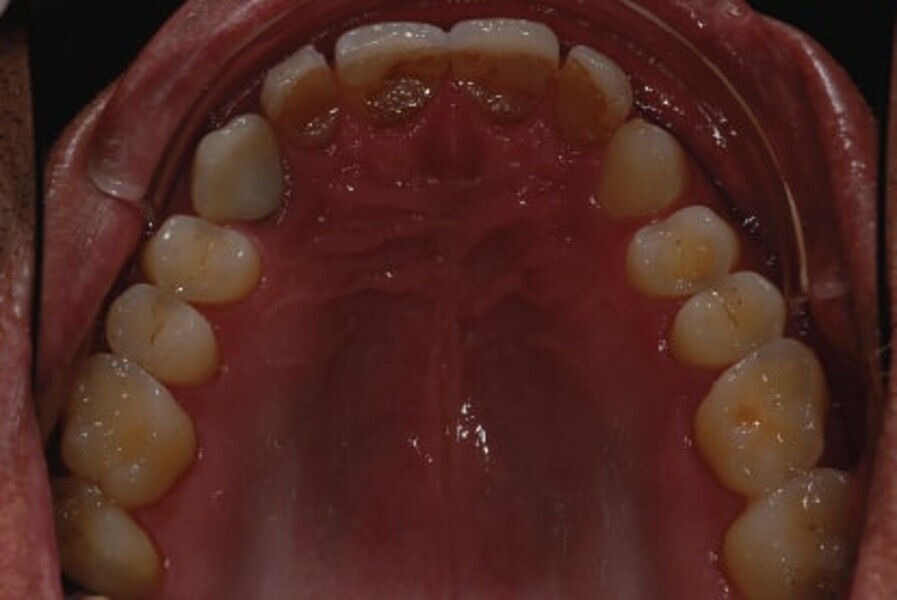

Fig. 2: Intraoral photograph prior to treatment, occlusal view of maxilla.